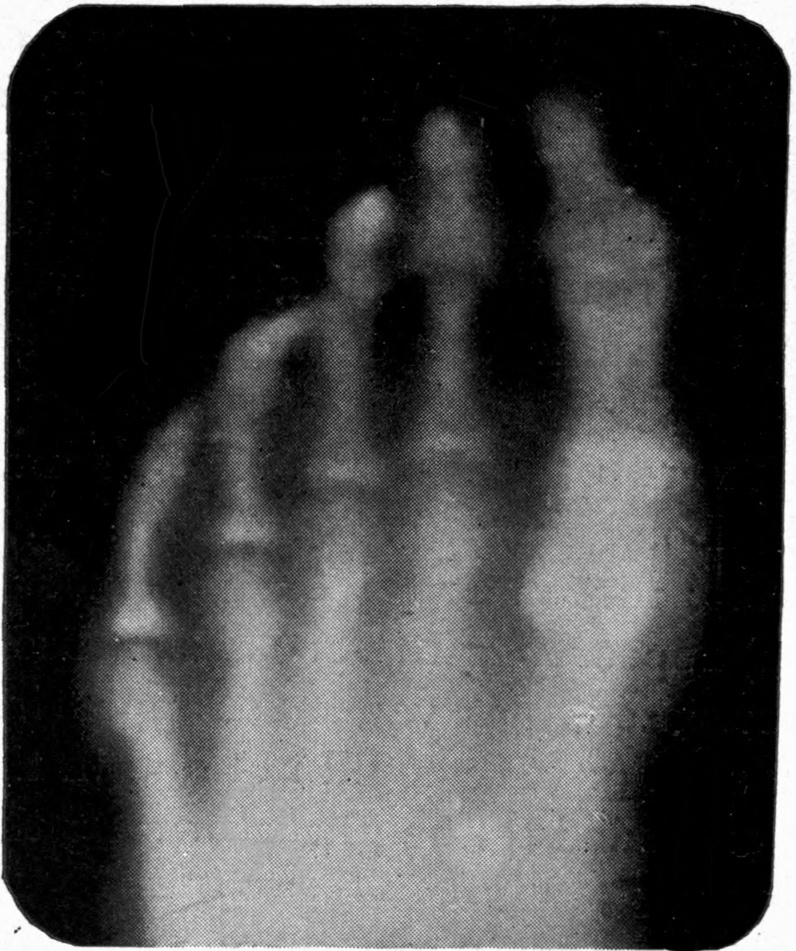

Fig. 1.—Head.

Fig. 2.—Broken Arm, Overlapping.

(Due to defective setting.)

Fig. 3.—Ribs.

Fig. 4.—Knee, Knickerbocker Buttons, Bullet in Femur.